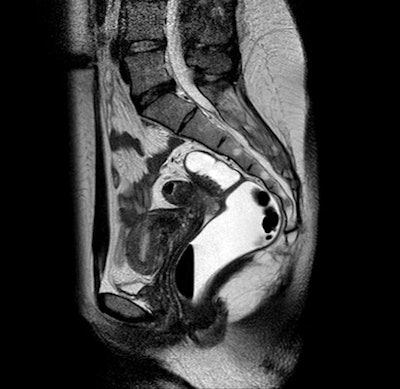

Endometriomas may be found in places such as on the ovaries, on the bowel wall, or on the bladder. Removal by surgical intervention is the standard treatment.

"Endometriomas can take on a variety of phenotypes, including cysts and adhesions, which adds to the difficulty of identifying them in MR images," Wenzel said.

MRI proved to be particularly reliable in the detection of endometriomas in the rear abdominal cavity and, with a detection rate of 90%, on the colon. This is significant because endometrial tissue is frequently overlooked in that region. In a number of cases, endometriomas grow into the colon wall and are difficult for the surgeon to see.

The method was somewhat less successful for the front abdominal cavity, in particular for the bladder and the uterine wall. MRI proved less helpful in detecting very small endometriomas.

Benefits of utilizing MRI include the fact that, for cysts, the technology shows metabolites, allowing to identify the age of the cysts and to differentiate endometrial from other types of cysts.